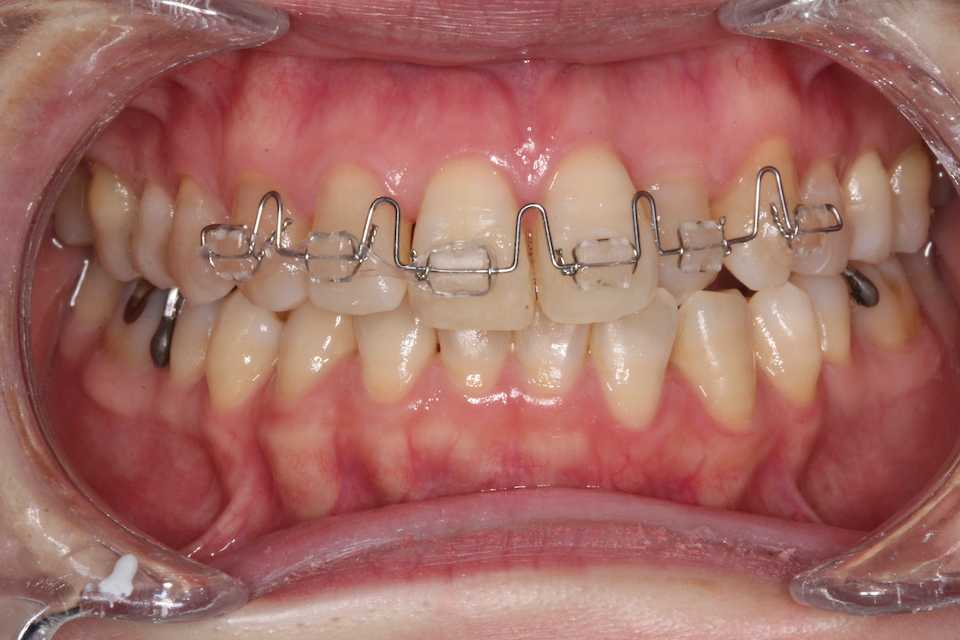

被蓋は改善したので微調整に入る。動かす必要のないところは連続結紮しておく。

角ワイヤーの016"-016"

2025/08/26